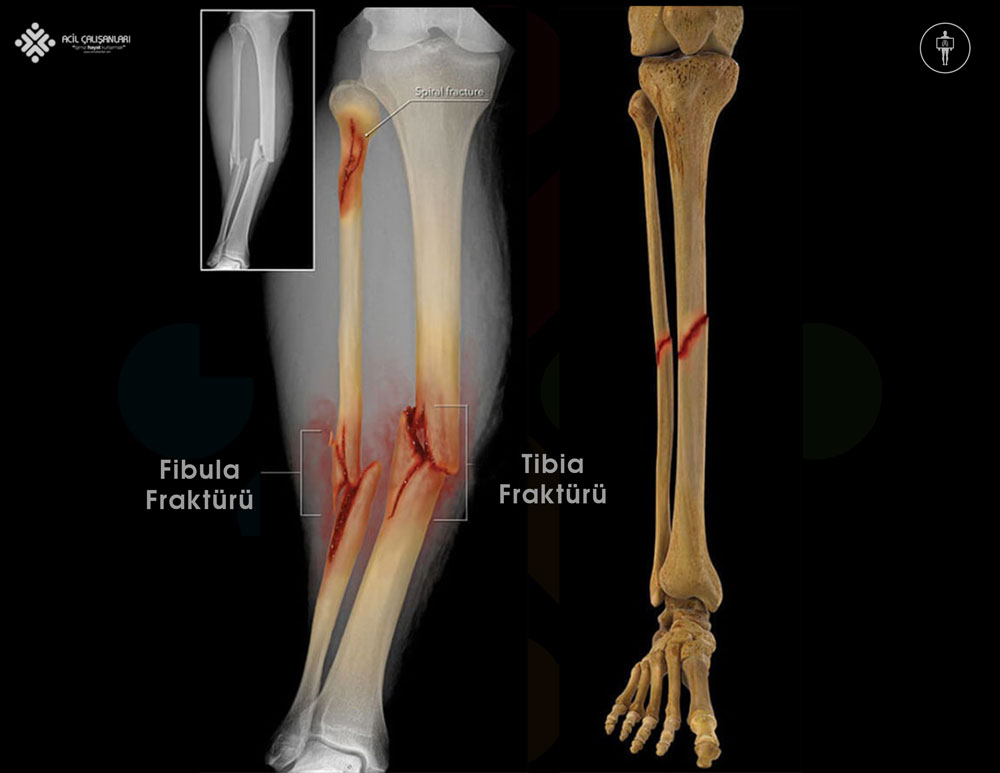

- Fibula Şaft Kırıkları: Fibula’nın orta kısmında, uzun kemik şaftında meydana gelen kırıklardır. Genellikle direkt travmalar veya burkulmalar sonucu oluşur. İzole fibula şaft kırıkları nadirdir ve genellikle tibia kırıklarıyla birlikte görülür.

Fibula, bacakta bulunan iki uzun kemikten biridir ve tibianın aksine, şaft açısından yük taşımayan bir kemiktir. Tibianın posterolateralinde yer alan fibula, çok daha küçük ve incedir. Bacakta lateral tarafta aşağı doğru uzanarak ayak bileği seviyesinde lateral malleolusu oluşturur.

Fibula ile tibia, medial yüzlerinde bulunan interosseous membrane (interosseöz zar) aracılığıyla bağlantılıdır. Bu sindesmoz bağ iki kemiğin stabiletisini sağlar ve çok sınırlı bir hareketlilik oluşturur.

İzole fibula şaft kırıkları çok nadir görülür ve genellikle bacağa doğrudan travma sonucu oluşur. Özellikle yakın zamanda bacağa doğrudan darbe almış ve fibula üzerinde palpasyonla hassasiyet bulunan bir hastada, fibula şaft kırığı düşünülmelidir. Bu tür bir durumda, fizik muayenede bacakta travma ile uyumlu olabilecek travma izi, ekimoz gibi cilt bulgularının değerlendirilmesi önem taşır. İzole fibula kırıkları nadir görüldüğünden, tüm ekstremitenin incelenmesi, özellikle o bölgenin üstündeki ve altındaki eklemlerin hareket açıklığının değerlendirilmesi gerekir.

Diz herhangi bir ligamentöz instabilite açısından kontrol edilmeli, ayak bileği ise herhangi bir yaralanma açısından dikkatle değerlendirilmelidir. Alt bacak röntgenlerine ek olarak, diz ve ayak bileğinin özel görüntülemeleri diğer kırıkları ekarte etmek açısından önemlidir. Fibula veya tibianın geri kalanında başka kırık olmaksızın fibula boynunda bir kırık tespit edilirse, bu durum sindesmotik yaralanmayı düşündürür ve “Maisonneuve kırığı” olarak adlandırılır. Benzer şekilde, ayak bileği ekleminin 15 cm yakınında bir fibula kırığı varsa, tibia kemik tutulumu, bağ yaralanması veya her ikisinin birden olması muhtemeldir.